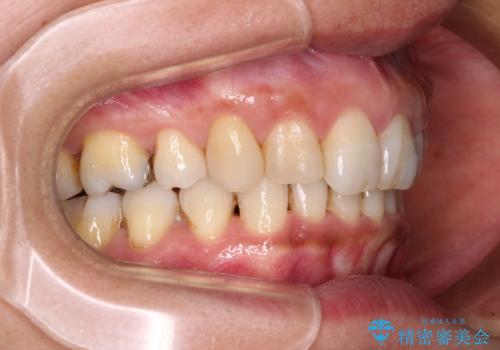

抜歯矯正の後戻りでできたスペース インビザライン矯正とセラミック治療

- 以前行った抜歯矯正が後戻りし、開いてしまったスペースが気になるとのことで来院された患者様です。

インビザラインを用いて開いてしまったスペースと前歯のデコボコを改善することとしました。

上顎前歯を左右対称となるように歯列を整えたいとのことでしたが、すり減って形態が大きく異なっていたため、できる範囲での仕上がりとなりました。